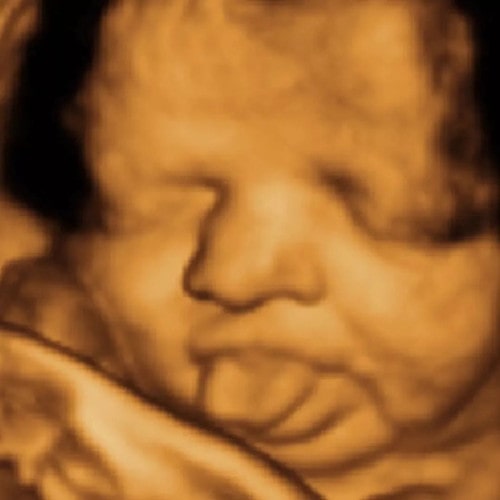

△婴儿像馋猫一样在妈妈肚子里舔胎盘

当妈妈吃掉自己喜欢的食物后,通过超声波甚至可以捕捉到肚子里的小馋猫在舔胎盘。